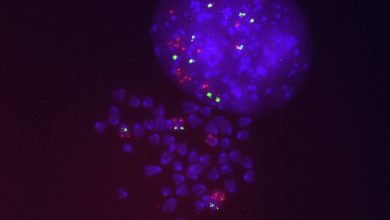

Cientistas identificam os mecanismos que levam à resistência ao tratamento do câncer de pulmão com Sotorasib

Células de câncer de pulmão resistentes a sotorasibe exibindo várias cópias do gene KRAS mutado (em vermelho) / CICANCER. Crédito:…